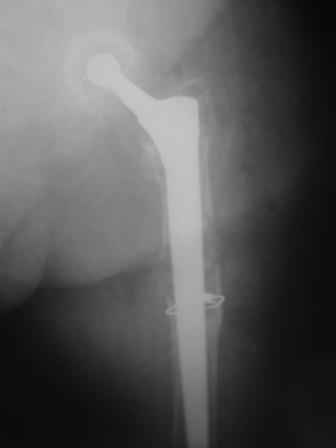

Спасибо за обсуждение. После нескольких дней тракции аппаратом сделали. Попытка закрытой репозиции не удалась из-за смещения по ширине, мешали фрагменты цемента. После их удаления репозиция получилась. Еще убрали немного цемента с ножки по латерльной стороне, чтобы обнажить 40-50 мм ее дистальной части, для плотной посадки гвоздя. Дальнейшее введение гвоздя было несложным. Протез показался нам стабильным в проксимальной части как латерально, так и медиально. Картинки в приложении.

THX for the discussion. After few days of traction by ex-fix the surgery was performed. An attempt of closed nailing was unsuccesful because of fragment translation, which was blocked by cement fragments. After removal of broken cement pieces reduction was reached "automagically". Also some cement from lateral part was removed by

chisel to expose distal 40-50 mm of the stem to allow tight fit of the nail. Further fixation by the nail was pretty easy and straightforward. Images attached. The stem looked stable in its proximal part both laterally and medially. Comments/critics are welcome.

I assume you preserved the medial fragment blood supply? If so, wow. very very nice. I'd like to stand and applaud your avoidance of strangulation cables around the medial fragment.

That's really a brilliant implant if the stem/nail interface is truly rigid.